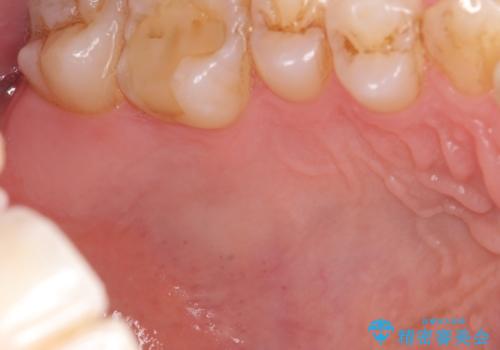

- 矯正前に下顎前歯の歯肉退縮の改善と予防のために歯肉移植を行った症例です。

上顎口蓋部から結合組織を採取し、下顎前歯部に移植しました。